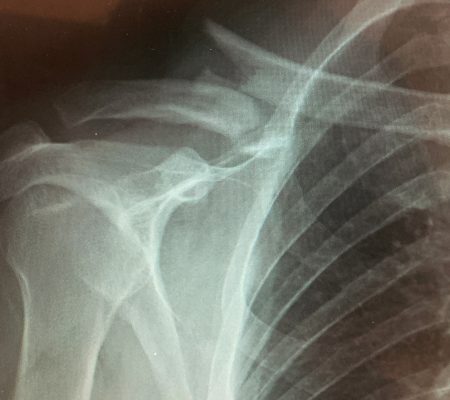

Dr. David Kornreich, one of the excellent surgeons at the Orthopaedic Hospital of Wisconsin, recently experienced a clavicle fracture requiring